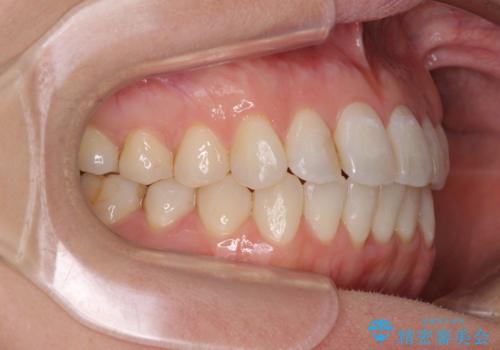

長年気にしていた前歯 インビザラインで目立たず改善

- ワイヤーではない矯正治療があると聞いたとのことで来院された患者様です。

長年前歯のデコボコを気にしていたもののワイヤー矯正に抵抗があり躊躇していたそうですが、インビザラインなら治療してみたいとのことで相談にいらっしゃいました。

インビザライン適用の歯列であったため、歯と歯の間を削るIPRを用いて改善することとしました。

下顎前歯の叢生が顕著な場合、歯列改善後に歯と歯と歯肉の間にブラックトライアングルという隙間ができてしまいます。

軽減することはできますが、完全に解決することは矯正治療のみでは不可能なため、リスクとして事前に周知しておく必要があります。